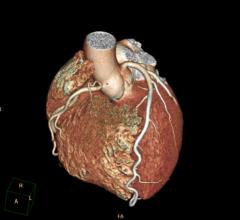

March 19, 2015 — Use of computed tomography coronary angiography (CTA), which provides 3-D images of the heart, coupled…

March 16, 2015 — Results from the PROMISE clinical trial confirmed what many cardiologists and radiologists have long…